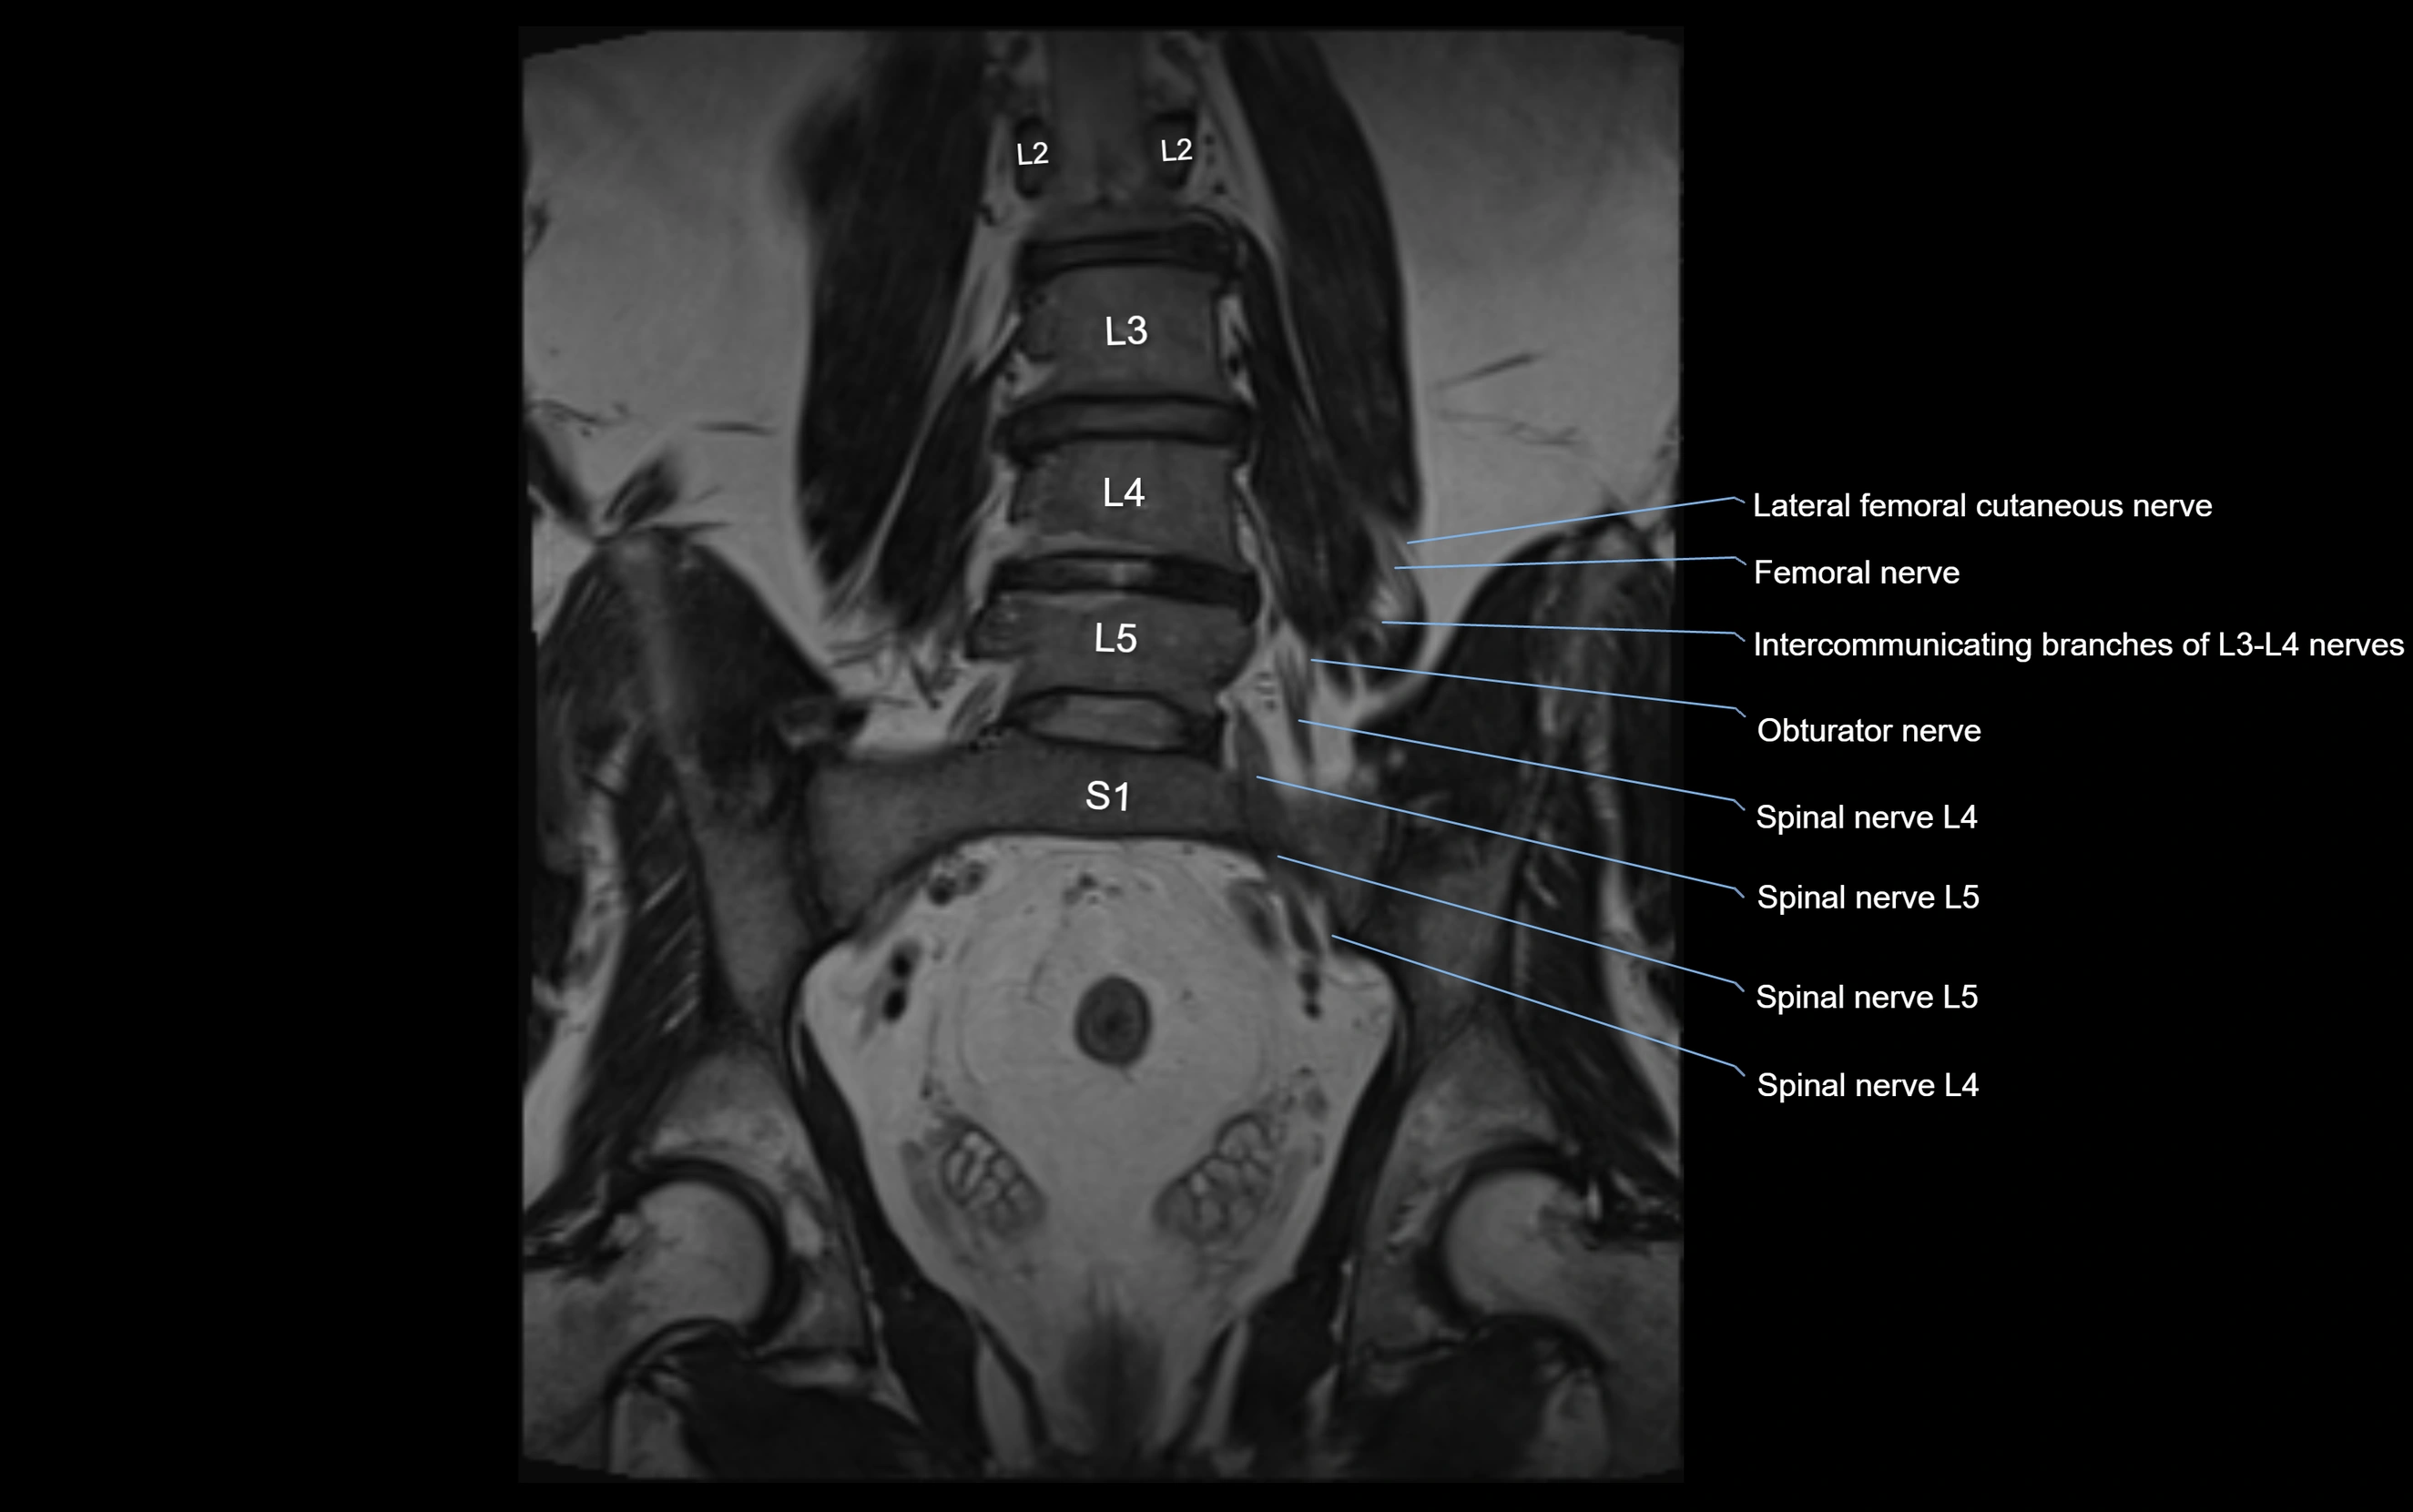

MRI Appearance

T1-weighted images:

• Nerve appears as a very thin low-to-intermediate signal intensity structure

• Surrounded by bright fat, aiding visualization

T2-weighted images:

• Nerve shows intermediate to mildly hyperintense signal compared to muscle

• Pathological involvement appears brighter

STIR (Short Tau Inversion Recovery):

• Normal nerve appears dark

• Inflamed or entrapped nerve appears bright hyperintense

T1 Fat-Sat Post-Contrast:

• Normal nerve enhances minimally

• Pathologic nerve (neuritis, entrapment, tumor infiltration) shows focal or diffuse enhancement

3D T2 SPACE / CISS:

• Nerve appears intermediate to mildly hyperintense compared to muscle

• Surrounded by bright fat or CSF, improving visualization

• Best sequence for mapping small pelvic nerves such as the anococcygeal